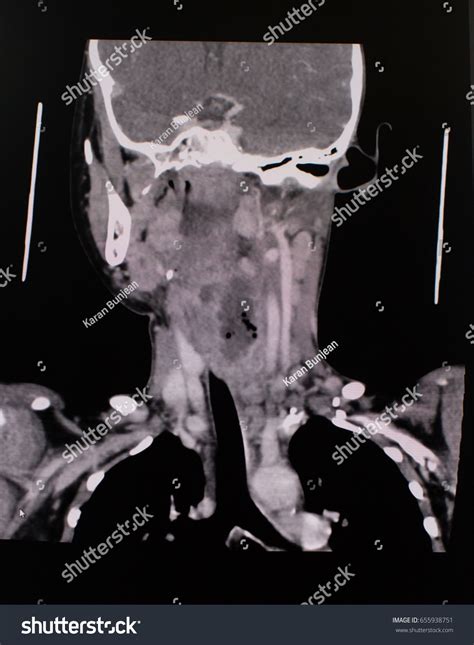

A CT scan of neck, often referred to as computed tomography, is a sophisticated diagnostic imaging procedure that utilizes X-rays combined with computer processing to create detailed, cross-sectional images of the structures within your neck. Whether your physician is investigating a persistent lump, evaluating unexplained pain, or monitoring a known condition, this imaging tool provides a level of clarity that standard X-rays cannot match. By capturing slices of the neck’s anatomy—including the thyroid gland, lymph nodes, blood vessels, and spinal structures—doctors can pinpoint abnormalities with remarkable precision, making it an essential component in modern diagnostic medicine.

The technology behind a CT scan of neck is fascinating. The patient lies on a motorized table that slides into a large, doughnut-shaped scanner. As you move through the scanner, an X-ray tube rotates around you, sending thin beams of radiation through your body. Detectors on the opposite side of the scanner record these beams, and the computer processes this information to create detailed, 3D-like images of the internal structures.